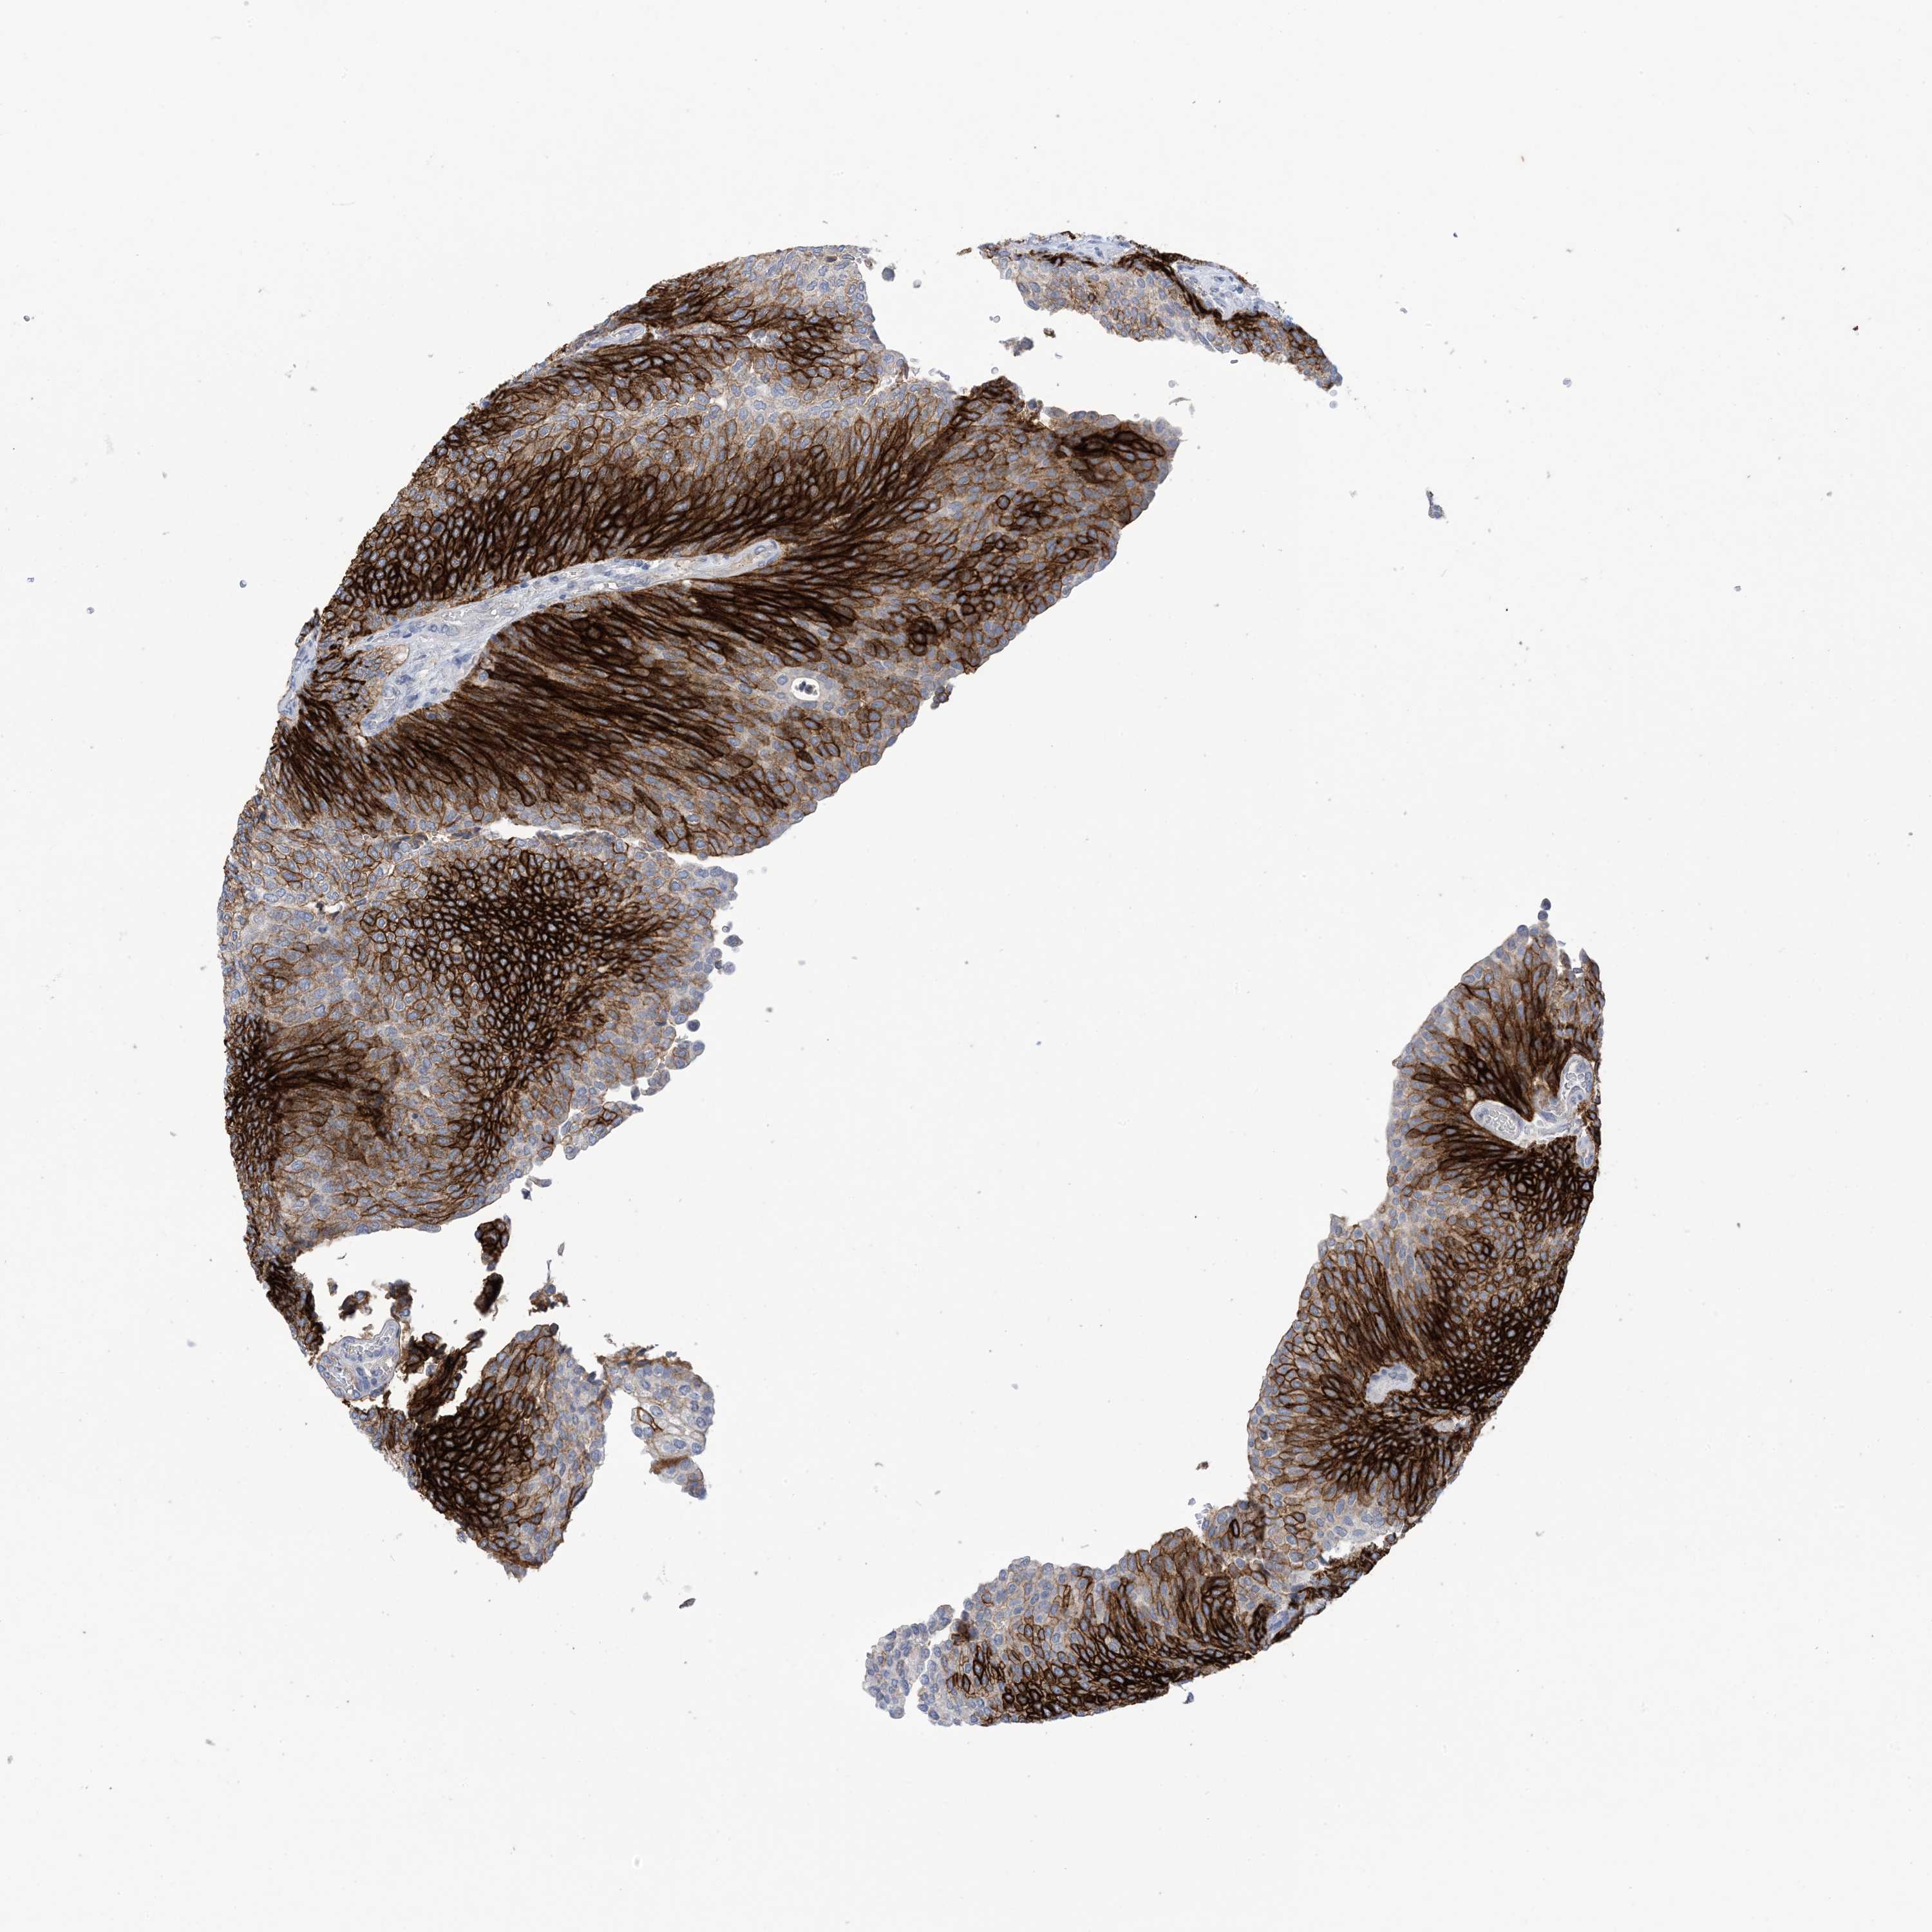

UROTHELIAL CANCER - Protein expressioni

A mouse-over function shows sample information and annotation data. Click on an image to view it in a full screen mode. Samples can be filtered based on level of antibody staining by selecting one or several of the following categories: high, medium, low and not detected. The assay and annotation is described here.

Antibody stainingi

Antibody staining in the annotated cell types in the current human tissue is reported as not detected, low, medium, or high, based on conventional immunohistochemistry profiling in selected tissues. This score is based on the combination of the staining intensity and fraction of stained cells.

Each image is clickable and will lead to virtual microscopy that enables deeper exploration of all samples and also displays staining intensity scores, fraction scores and subcellular localization as well as patient and tissue information for each sample.

Antibody HPA049265

Antibody CAB037328

Urothelial carcinoma, High grade

Urothelial carcinoma, Low grade

Urothelial carcinoma, NOS